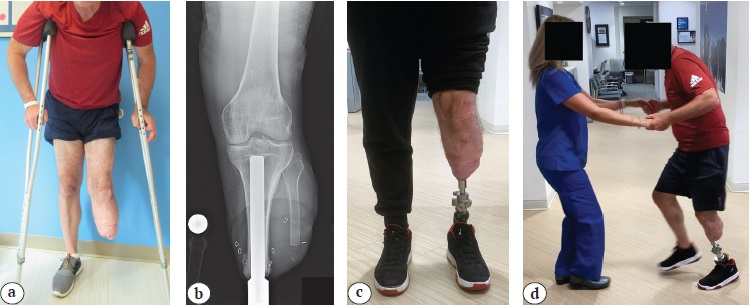

The largest civilian study of TOFA in the United States was performed by T.J. Reif et al. [6]. Evaluating 18 transfemoral and 13 transtibial amputees who underwent osseointegration, patients reported significant improvements in prosthesis wear time, mobility, and multiple quality-of-life surveys. With an average follow-up of nearly 2 years, all quality of life domains improved significantly, with increased prosthetic use and comfort and fewer prosthesis-related complications. All patients who were unable to use a TSP prior to surgery were able to ambulate independently with the osseointegrated prostheses. The study also found improvements in overall pain and pain interface, suggesting reduced discomfort enabling enhanced mobility. Although acute complications, such as mechanical issues and soft tissue infections, were noted, all were managed without the need to remove any implants. The study also noted significant improvements in mental health, overall health, physical health, and functionality, as reflected in higher PROMIS scores. These findings, along with patient-reported improvements in activity, self-image, and appearance, reinforce the growing body of literature that osseointegration offers substantial benefits over TSP. One further notable aspect of this article is the relatively large number of tibial amputees represented. There is very little literature describing TOFA for transtibial amputees, even though the procedure can often be exceptionally empowering for them as well as for the transfemoral patients (Figure 2).

Figure 2. Transtibial osseointegration: a — preoperative photograph identifies this patient is using two crutches to locomote because of his inability to wear a socket prosthesis due to pain; b — X-ray in the anterior-posterior view depicting the transtibial osseointegration implant; c — standing photograph of the patient following transtibial osseointegration; d — photograph showing the patient feeling comfortable and enthusiastic enough to initiate a dance with the nurse during the postoperative visit. Note that the patient is able to plant on the osseointegrated limb confidently enough to lead his partner while having his intact leg off the ground